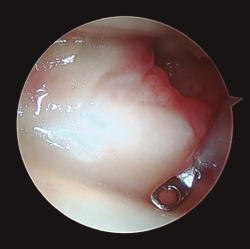

- Artroscopia de muñeca con sistema de tracción longitudinal a 10 N y vías artroscópicas estándar 3-4 y 6R para evaluar la articulación radiocarpiana y las vías mediocarpiana ulnar (MCU) y radial (MCR) en el caso de la articulación mediocarpiana, utilizando para ello una óptica de 2,3 mm y 30°(2,17), mediante técnica de artroscopia en seco(23)(Figura 2). En este tiempo quirúrgico artroscópico se evaluó: la presencia de escalón articular, la rotación de los fragmentos articulares y la existencia de lesiones asociadas al nivel del complejo del fibrocartílago articular (CFCT), así como al nivel de los ligamentos extrínsecos e intrínsecos de la muñeca(17)(Figura 3). En primer lugar, se evalúo la articulación radiocarpiana y, a continuación, la articulación mediocarpiana.

Figura 3. Desde el portal de visión radiocarpiano 3-4 observamos un importante escalón articular en la superficie de la extremidad distal del radio. Al fondo de la imagen se aprecian los ligamentos radiocarpianos volares, con integridad de los mismos.